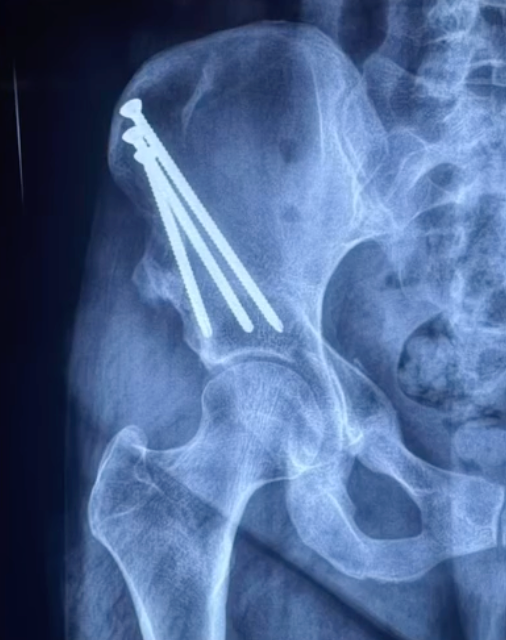

X-rays: measure hip socket coverage and alignment.

Periacetabular Osteotomy (PAO)

The gold-standard procedure for adult hip dysplasia. In this surgery, the surgeon repositions the acetabulum (hip socket) to provide better coverage of the femoral head.

Improves hip stability.

Protects cartilage from further damage.

Can delay or prevent arthritis.

Best suited for younger patients with preserved joint surfaces.